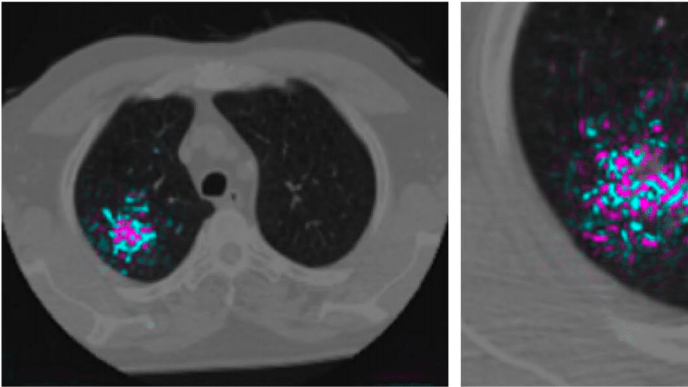

Intelligenza Artificiale Una AI potrebbe rilevare il cancro ai polmoni più rapidamente ed efficacemente Una nuova ricerca condotta da Google mostra come l’apprendimento automatico potrebbe un giorno…Will Knight20/05/2019